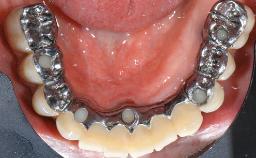

In 2004, the patient, a smoker, began dental treatment at the ACTA graduate clinic. She was a TV producer exposed to a lot of stress in her job and had a sick husband. Her maxillary teeth had been extracted, as had the mandibular canines, premolars, and molars, with the exception of tooth 34. She received a complete maxillary denture and a mandibular skeleton denture. In October 2007, her maxilla was augmented by an oral and maxillofacial surgeon; in March 2008, implants (Biomet 3i, Palm Beach, Florida, USA) were inserted at that same clinic. In 2008, the patient was presented at the Department of Oral Implantology and Prosthetic Dentistry to request restorations for her implants. An implant-supported overdenture was planned. She also asked if we could restore her occlusion with fixed prosthetics.

| Bone Volume | Deficient horizontally, requiring prior grafting |

| Defining Characteristics | Fully edentulous upper jaw to be rehabilitated with an implant-borne removable overdenture |